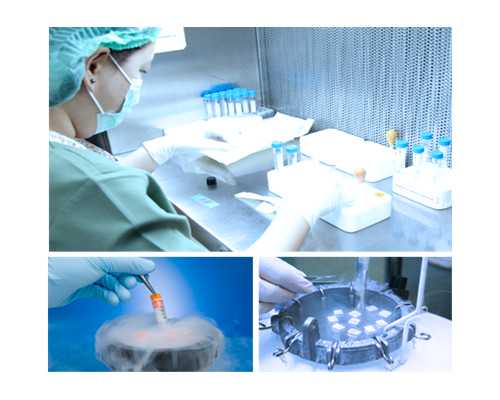

試管嬰兒技術(shù)一般是指體外受精技術(shù),是在實驗室條件下進行的一種技術(shù),其特點是在實驗室條件下將精子和卵子放在一起,使精子和卵子進行結(jié)合,達到受精的目的。試管嬰兒技術(shù)進入周期后,具體能做多久取決于女性的月經(jīng)周期。正常情況下,月經(jīng)周期為 28-32 天,受精的最佳時間通常是月經(jīng)周期的第 11-14 天,也就是排卵期。

檢查是試管嬰兒周期的重要組成部分。為了最大限度地提高試管嬰兒的成功率,夫妻雙方都應(yīng)為檢查做好準備,以確保受精的準確性。